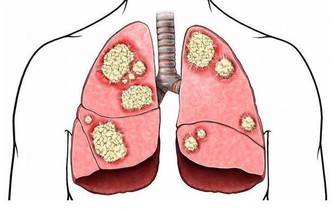

嚴重缺硒則導致免疫力低下、視力減退、易患心血管疾病和腫瘤。